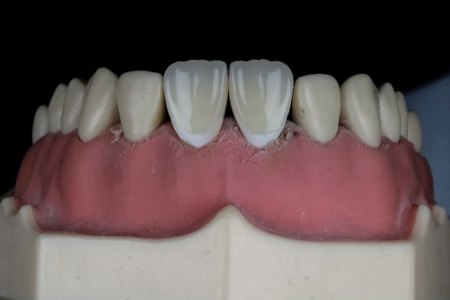

Totalne i subtotalne proteze

Gubitak zuba je čest problem koji utiče ne samo na izgled, već i na žvakanje, govor i opšte samopouzdanje. Kada nedostaje veći broj zuba, pacijenti se često...